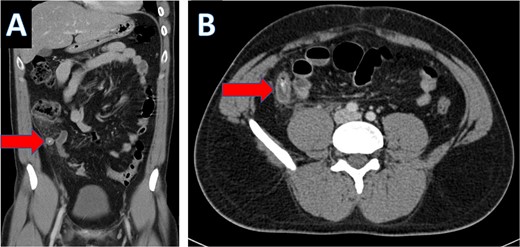

Multiple tiny obstructive stones were also noted bilaterally. The appendix measured approximately 1.4 cm in maximum caliber, with an appendicolith present within the appendiceal lumen (Fig. 3a). Significant surrounding fat stranding was noted around the appendix, and multiple enlarged lymph nodes with signs of reactive inflammation were seen adjacent to the cecum (Fig. 3b).

Coronal CT scan showing appendicolith (A) and axial CT showing appendicitis (B).